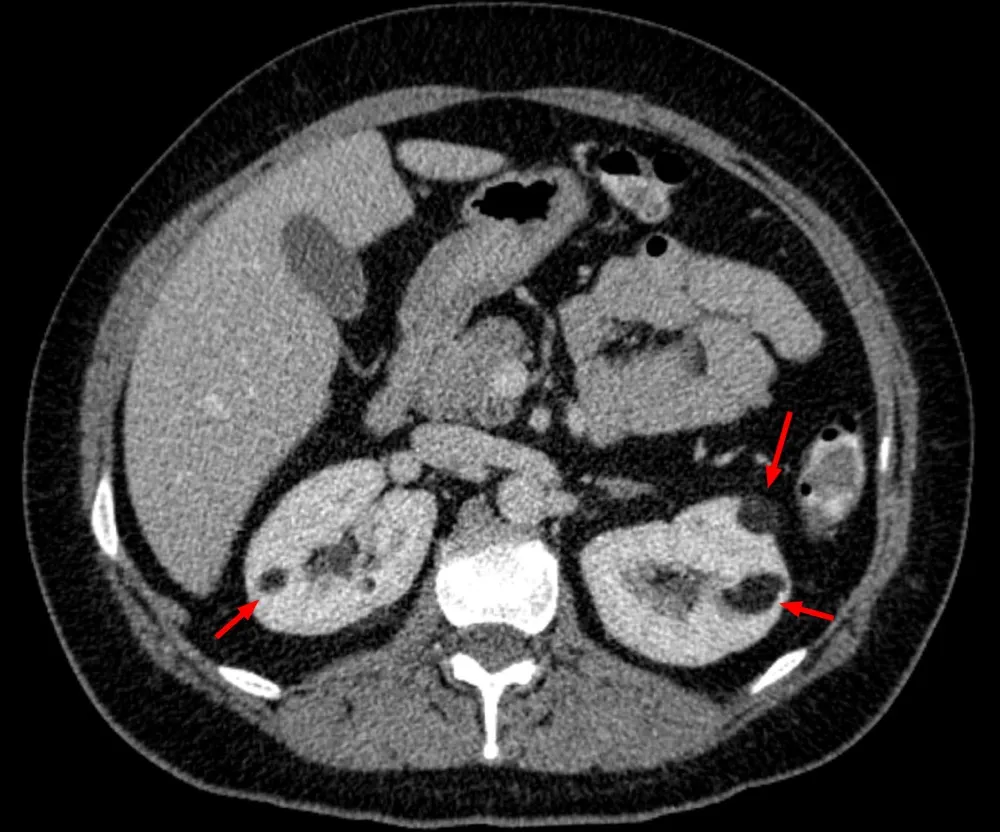

* Pacientes com **AML múltiplos (≥3), bilaterais e/ou grandes(ou seja, ≥4 cm)** têm maior probabilidade de ter CET (imagem abaixo).

TC abdome sem contraste evidenciando imagens hipodensas na região cortical de ambos os rins